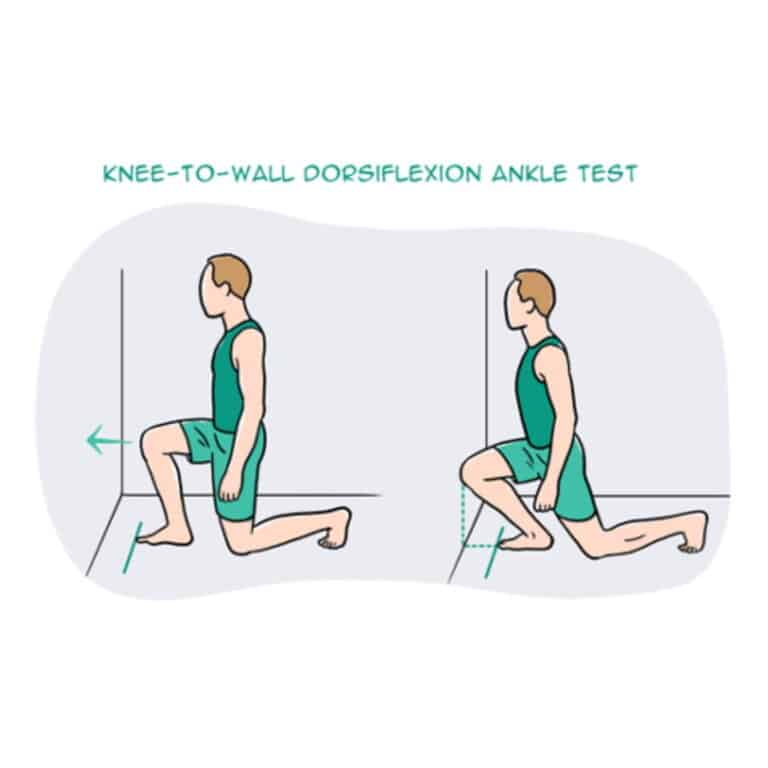

เอ็นร้อยหวายอักเสบ (Achilles Tendinitis) อาการ สาเหตุ วิธีรักษา … ท่าบริหารเอ็นร้อยหวาย แก้เอ็นร้อยหวายตึง เอ็นร้อยหวายอักเสบ เอ็นร้อยหวายบวม

ท่าบริหารเอ็นร้อยหวาย แก้เอ็นร้อยหวายตึง เอ็นร้อยหวายอักเสบ เอ็นร้อยหวายบวม 1Pc Nkle สายรัดข้อมือเอ็นร้อยหวายรั้ง Sprain ป้องกันผ้ารัดข้อเท้าปลอก …

[Sahavate] รู้หรือไม่! การออกกําลังกายแบบ Plyometric และ Eccentric … ท่าบริหารเอ็นร้อยหวาย แก้เอ็นร้อยหวายตึง เอ็นร้อยหวายอักเสบ เอ็นร้อยหวายบวม

ท่าบริหารเอ็นร้อยหวาย แก้เอ็นร้อยหวายตึง เอ็นร้อยหวายอักเสบ เอ็นร้อยหวายบวม เช็คด่วน! สัญญาณเตือนเอ็นร้อยหวายอักเสบ ที่คนรักออกกำลังกายต้องรู้

เอ็นข้อเท้าอักเสบเกิดจากอะไร ? – คลินิกกระดูกและข้อ (หมอสุทธิ์) ท่าบริหารเอ็นร้อยหวาย แก้เอ็นร้อยหวายตึง เอ็นร้อยหวายอักเสบ เอ็นร้อยหวายบวม

ท่าบริหารเอ็นร้อยหวาย แก้เอ็นร้อยหวายตึง เอ็นร้อยหวายอักเสบ เอ็นร้อยหวายบวม juscomart สเปรย์รักษาปวดส้นเท้า เอ็นร้อยหวายอักเสบ SAISHI | Lazada.co.th

ท่าบริหารเอ็นร้อยหวาย แก้เอ็นร้อยหวายตึง เอ็นร้อยหวายอักเสบ เอ็นร้อยหวายบวม แยกให้ออก! ปวดข้อเท้าด้านหลัง เอ็นร้อยหวายอักเสบ หรือ ถุงน้ำหลังข้อเท้า …